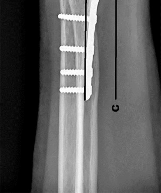

Question 12:

When executing a posteromedial approach to the knee for open reduction and internal fixation of a posteromedial tibial plateau fracture, the surgeon must develop a plane. The optimal inter-nervous/inter-muscular interval is primarily developed by retracting the medial head of the gastrocnemius laterally and which structure medially?

Correct Answer: Pes anserinus

Explanation:

The posteromedial approach to the tibial plateau typically utilizes the interval between the medial head of the gastrocnemius (which is retracted laterally, protecting the neurovascular bundle in the popliteal fossa) and the pes anserinus (sartorius, gracilis, semitendinosus), which is retracted medially/anteriorly. The semimembranosus can also be retracted medially. The pes anserinus forms the medial boundary of this superficial dissection window.